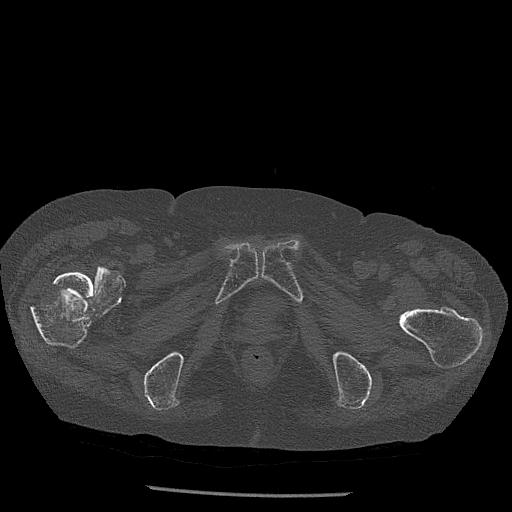

100703 1/27 両股正面+軸 1/29 両股正面+軸 94歳女性 パンソンロン

46666 1/23 両股正面+軸と右手関節 2R 76歳女性 右橈骨遠位端

46666 1/28 両股正面+軸と 1/26 右手関節 2R 76歳女性 右転子部骨折

37 1/18 両股正面+軸 1/22 2R 86歳女性 右転子下

91569 3/25 両股正面とラウエン 70歳女性 人工骨頭+バンクーバー